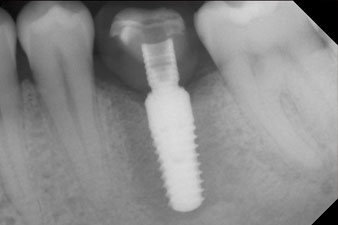

The torque used for the machine-driven placement was 43 Ncm. In addition, after screwing a measuring post (SmartPeg) specially matched to the implant, the ISQ value was measured with the probe of the W&H Osstell ISQ module.

This module is an optional extra for the W&H Implantmed and is docked to the implantology motor (see Fig. 11). The dimensionless ISQ value immediately after insertion was 64 orovestibular and 68 mesiodistal (maximum value = 100).

These values could have indicated open healing or even immediate restoration. Due to the insufficient crestal bone volume at the implant, the region was augmented with the bone chips collected during preparation of the implant bed and sutured to exclude saliva.